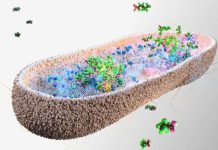

By discovered a previously unknown and nasty side effect of a bacteria-fighting weapon in the immune system’s arsenal called neutrophil extracellular traps (NETs), scientists finally understand that NETs are responsible for directly enhancing the production of harmful Th17 cells. This discovery is opening doors to the development of future therapies that can hinder the harmful NET-Th17 interact that is causing so much harm – therefore improve treatments for MS and several other autoimmune diseases.

NETs capture and kill nasty bacteria, they’re designed to protect the body from infection however it has become clear that they have the ability to manipulate Th17 cells making them stronger and more dangerous. “We found that the NETs cause Th17 cells to become more powerful, which enhances their detrimental effects,” senior author Associate Professor Anne Bruestle, from the ANU Department of Immunology and Infectious Disease, said.